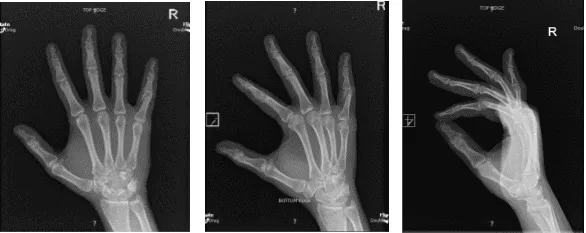

Rayos X Mano derecha mínimo 3 años